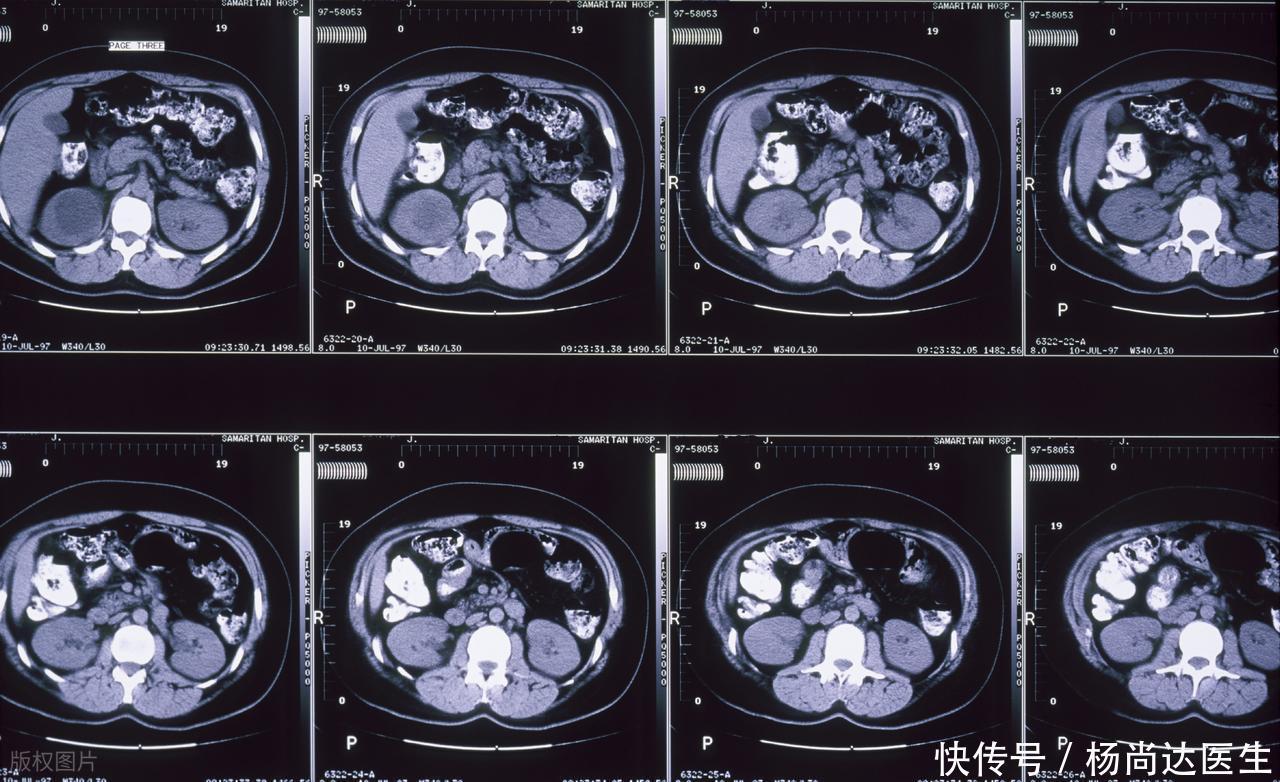

这事儿得这么想,影像学看的是密度的差异,是组织含水量和细胞浓密程度的综合表现,一个密度轻微下降的区域,说明那块地方的细胞结构可能正在水肿,或者已经开始分解,这与单纯的脂肪沉积看起来有明确的差别,就像新刷的墙面和正在渗水的墙面,视觉感受是截然不同的,需要用专门的数学模型估计其射频衰减百分比来做判断。

区分的关键点,往往隐藏在动态变化和细微的边界处理上,良性的单纯囊肿,边缘是光滑的,内部回声均匀得像一汪清水,而早期的感染灶,往往在边界处有类似“毛刺”的结构,或者在特定的造影剂作用下,它周边的肝组织会显示出高血管性的反应,这种“边上的激动反应”,是单纯囊肿所不具备的征象,反映出机体正在对入侵物发起一场局部战斗。